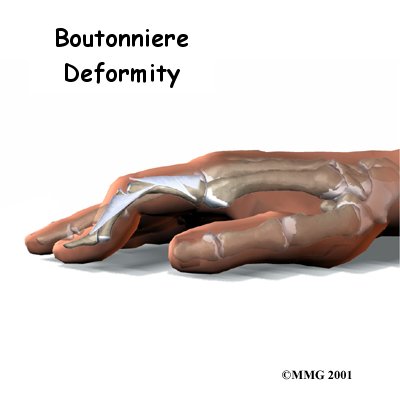

Boutonniere Deformity of the Finger

The tendons that allow each finger to straighten, the extensor tendons, at first appear to be relatively simple. But as the extensor tendon runs into the finger, it becomes a complex and elegantly balanced mechanism that allows very fine control of the motion of each joint of the finger. When this mechanism is damaged in certain areas, this balance can be destroyed. The result is a finger that doesn't work properly. Over time, the imbalance can lead to contractures (tightening of the tendons) an...